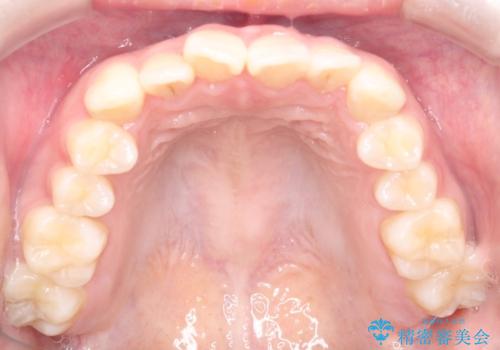

【インビザライン】前歯の凸凹をなおしたい

- 前歯のガタガタを主訴に来院されました。

インビザラインで綺麗な歯並びになり、患者さんには大変満足していただきました。

インビザラインは軽度叢生治療において優れた選択肢となります。